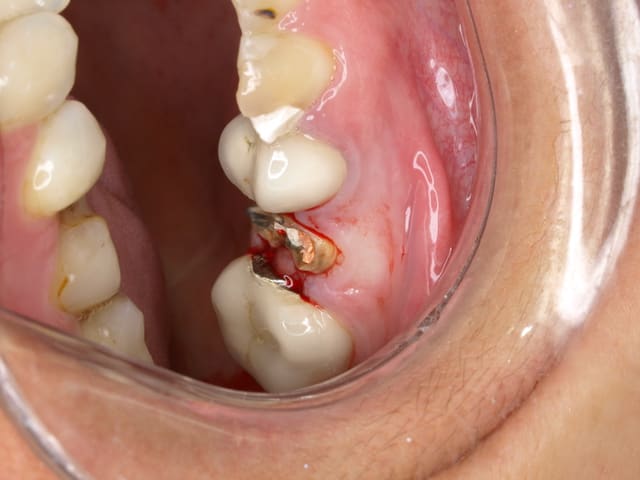

oui elles sont solidarisée .ca change rien je les ai separées comme on peut le voir sur la photo 2

La couronne semble bien, le tenon aussi.

Le traitement endo bien que pas très radio opaque semble bon.le traitement endo a été fait il y a un moment d après ce que tu dis.

Peut être une fracture?, une fissure ou un abcès endo- paro?

tu vois la sortie de l absces et loin de la racine .

donc il y a pas mal d os en vestibulaire

donc ce ne peut pes etre une fracture radiculaire.

et comme les endo sont anciennes elles sont pas en causes

Mais je ne vois pas de causes particulière a par une effraction du tenon en vestibulaire?

Non, parceque sinon l abcès serait plus haut.....

a mon avis la dentiste a foré la racine pour preparer l inlay core et a du decoller le cone de gutta.

lors du scellement de l inlay core ,le ciment a du fuser a l apex et necroser l os sous jacent

BINGO la bestiole apparait a l apex . tu vois le petit machin blanc qui est sorti ?